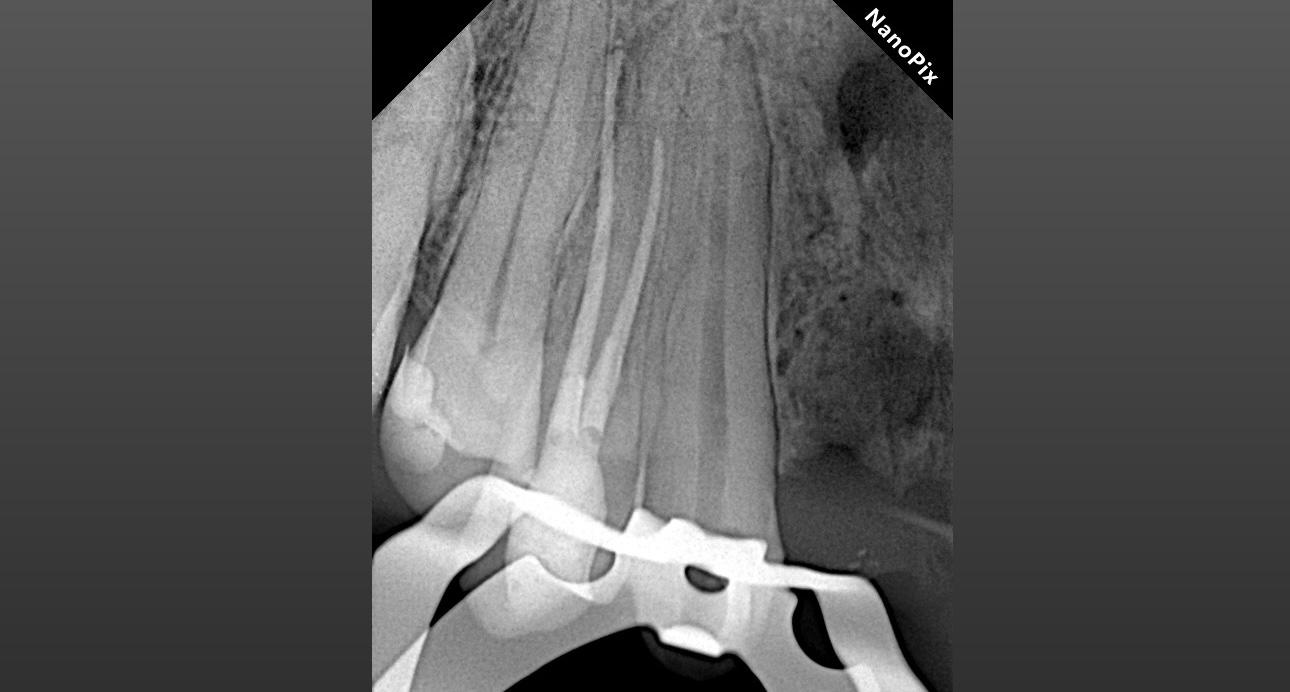

1.3 Хронический апикальный периодонтит.

Длина корневого канала 24 мм.

Дезобтурация Sani retreatment. Важно работать от корональной трети, постепенно двигаясь в апикальном направлении. Не стремиться сразу пройти на всю длину канала.

Инструментация Soco SC до 45/04. Финишный инструмент до чистых опилок на кончике файла.